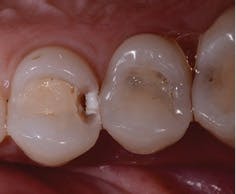

My consultation/diagnosis process begins with these three amazing technologies. SoproLife is an intraoral camera with high image quality, the capacity to diagnose and treat caries, and the capability for image magnification of 30 to 115 times. Here is the science behind this device: It uses a patented fluorescence technology that absorbs luminous energy and emits it as fluorescent light. The tooth is illuminated by this 450 nm wavelength of light, and the tissues are characterized by autofluorescence, colorizing the tooth in red, green, and blue hues - depending on the type of caries or the type of crack. It has three modes: daylight mode for intraoral imaging, diagnosis mode for detection of caries, and treatment mode for usage during the excavation process. The SoproLife lets me differentiate healthy tissue from infected tissue to help me identify the affected areas to excavate and aid me in removing all diseased tissue, while preserving as much healthy tooth structure as possible.

We use the SoproCare device in our hygiene area during prophylaxis and periodontal treatment. It uses the science of fluorescence with a specific wavelength of light between 440 nm and 680 nm. This device illuminates dental tissue to reveal caries, as well as tartar and plaque. According to the company, it is also the first product on the market to reveal gingival inflammation. Chromatic amplification differentiates the color of the tissue. Because of the easy-to-see color-coding, the hygienist can show the patient the hues of red that indicate gingival inflammation: "Look at your gums and see how red they are; that is due to plaque." Similar to the SoproLife, this device also has three modes: daylight mode for intraoral imaging; perio mode for plaque, tartar, and gingival inflammation imaging; and cario mode for detection of occlusal caries.